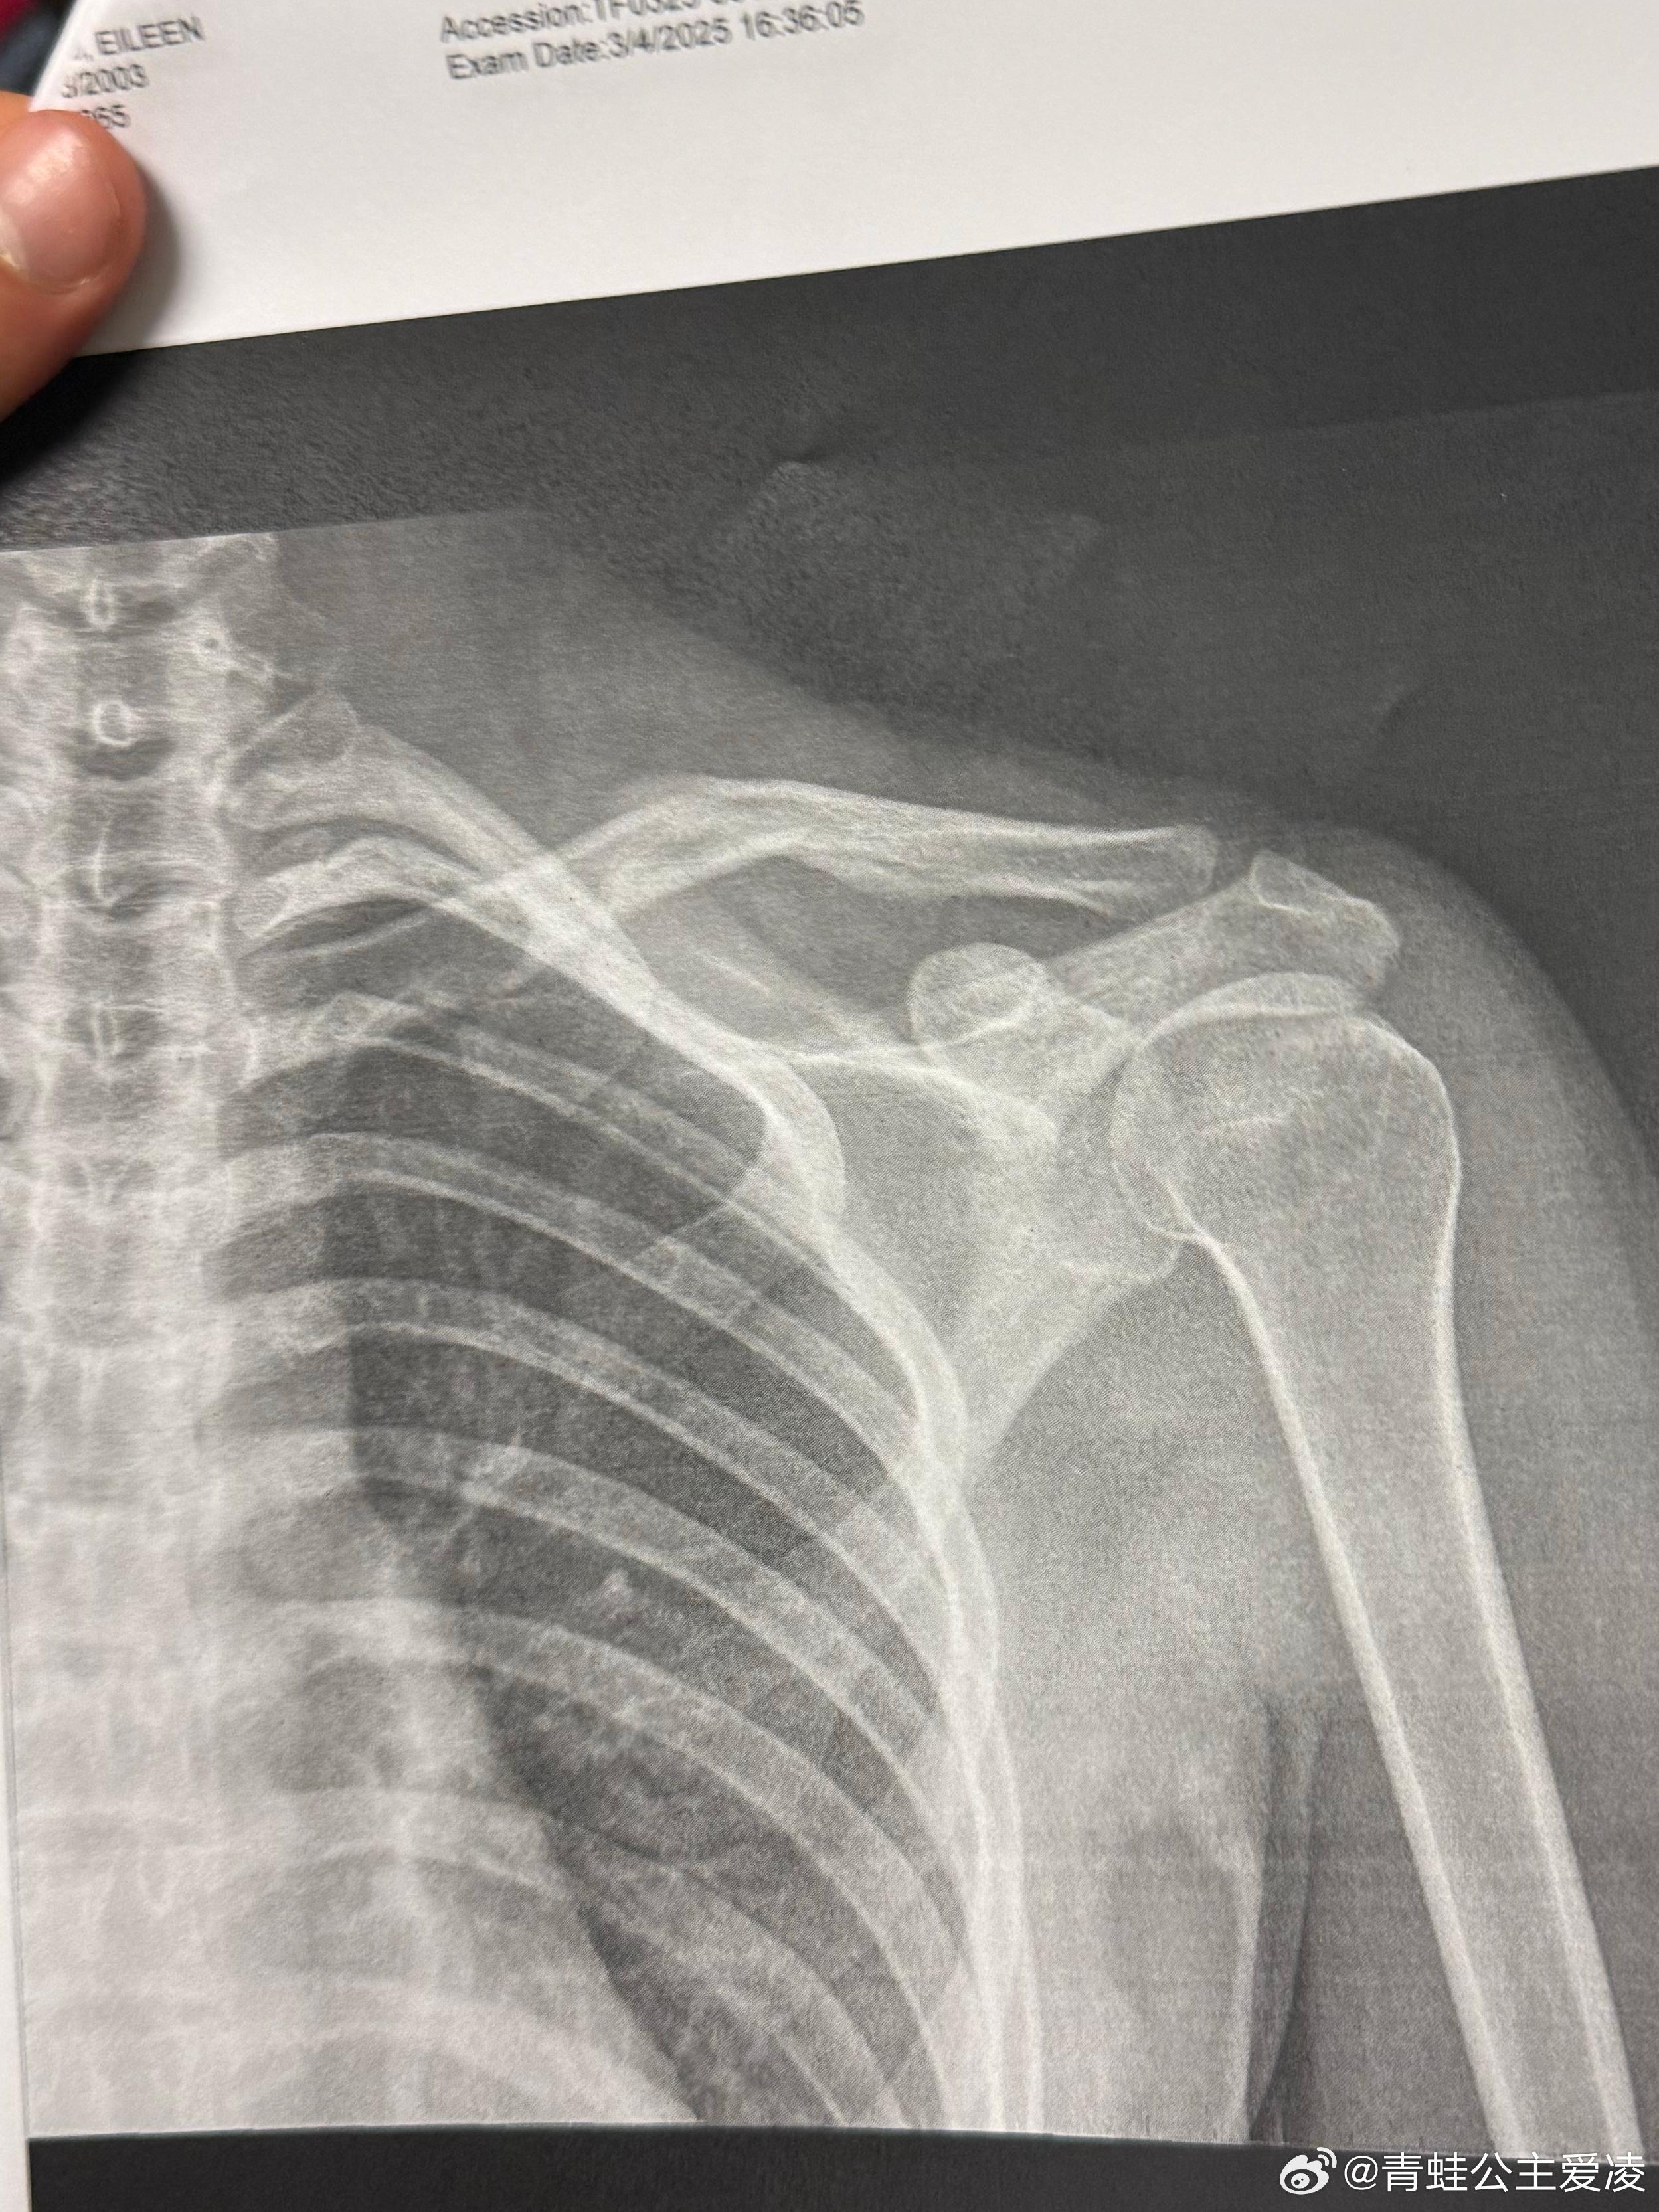

3月9日,谷愛凌在社交平台上載了肩部骨折的X光照片,並配上「心碎」的表情。這消息迅速衝上微博熱搜,令網友十分心痛,紛紛送上祝福:「注意身體,早日康復,期待你重回賽場! 」還有人引述巴黎奧運金牌得主全紅嬋的經驗,認為谷愛凌可能和全紅嬋一樣,「隨著年齡增長,身體各部分重量變化了,整體協調性要有個適應過程, 這段時間內做動作可能就各種轉不過來」。

據先前傳媒報道,谷愛凌上月4日曾在微博發文稱,「我在Aspen Xgames(冬季極限運動)比賽受傷後,為了能參加緊接其後的世界盃比賽,在訓練中不幸再次受傷。今天我不得不懷着沉重的心情退出盼望已久的哈爾濱亞冬會。」